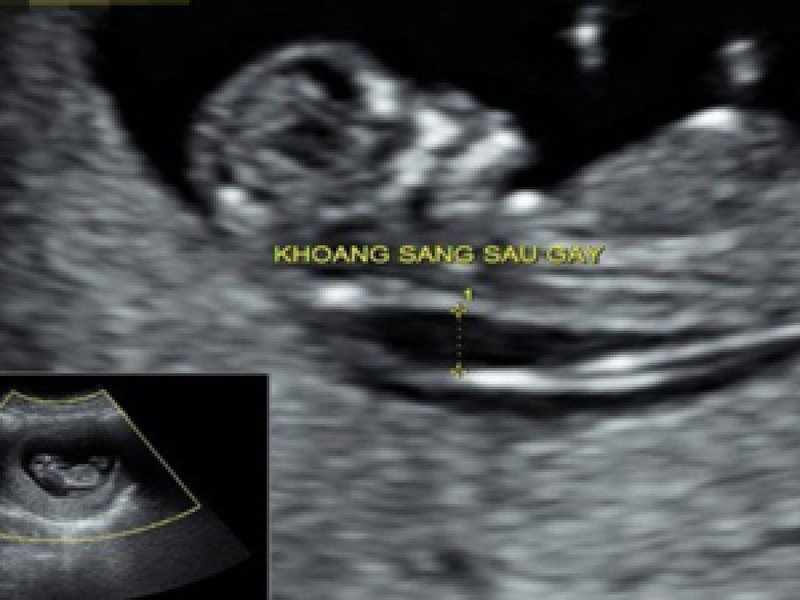

Độ mờ da gáy (hay khoảng sáng sau gáy) là sự kết tụ của chất dịch dưới da ở vùng gáy của thai nhi. Tất cả bé ở tuổi thai từ 11 tuần - 14 tuần đều có kết tụ chất dịch này ở vùng gáy. Thực hiện đo độ mờ da gáy để kiểm tra vùng da gáy ở bé bằng cách siêu âm thai giúp bác sĩ chẩn đoán sớm nhất về nguy cơ mắc hội chứng Down, từ đó tư vấn xem người mẹ có cần làm thêm xét nghiệm sàng lọc trước sinh NIPT hoặc một số xét nghiệm cần thiết khác hay không.

Độ mờ da gáy là sự kết tụ của chất dịch dưới da ở vùng gáy của thai nhi. Độ mờ da gáy là sự kết tụ của chất dịch dưới da ở vùng gáy của thai nhi